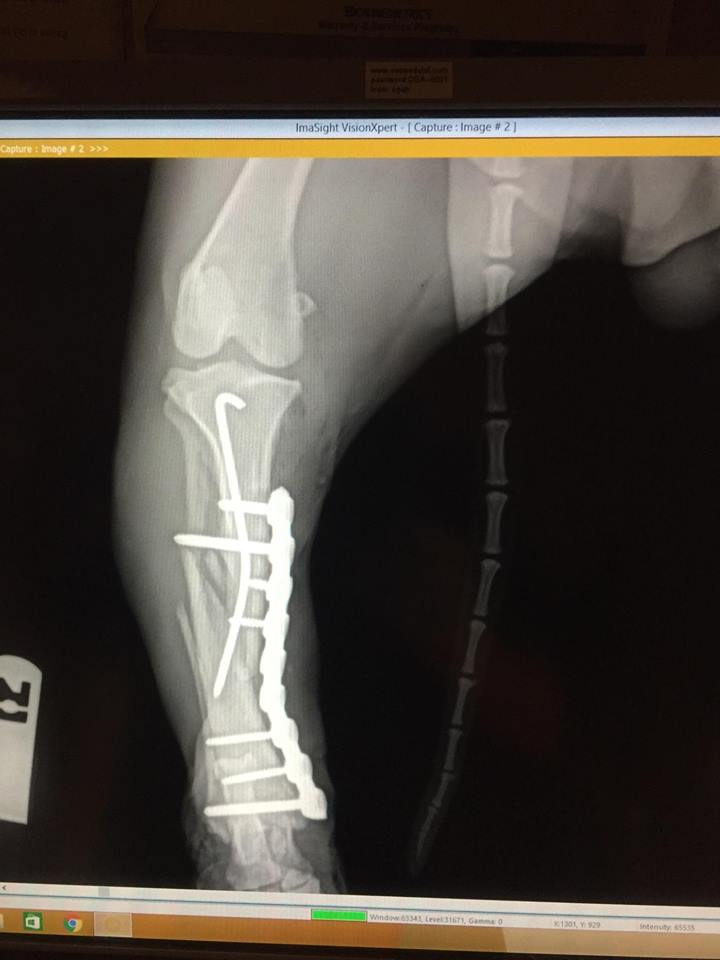

Broken elbow, 12 week old Chihuahua

Canine, month-old fracture repair

Bone plating, Feline